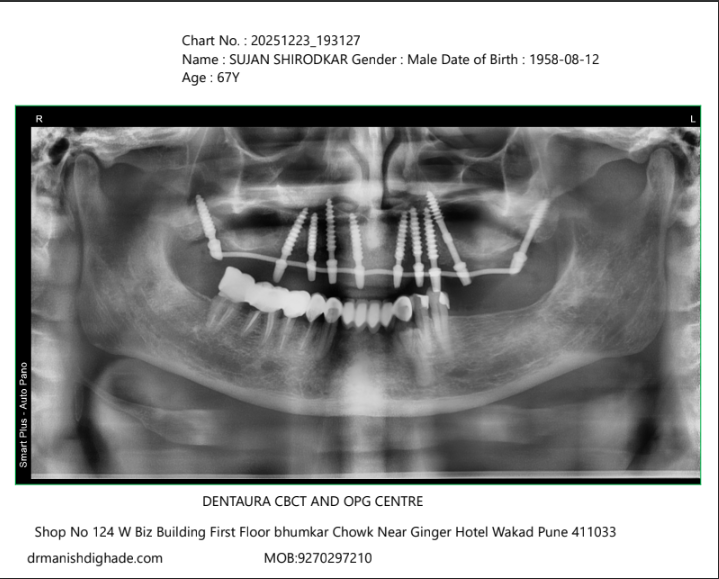

X-Ray Analysis

OPG — After

Radiographic Findings

The OPG shows successful placement of implants in the upper arch, providing stable support for fixed teeth. Proper distribution of implants ensures long-term strength and function.